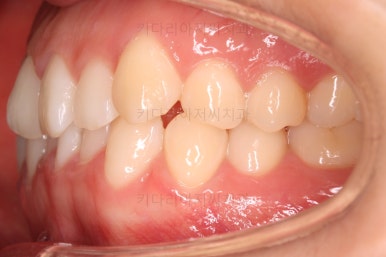

초진 시 입안의 모습이에요.

입을 다물고 있을 때는 자연스러운 다물림이나 옆라인 등 모두 양호해요.

입을 벌리거나 말할 때는 앞니가 삐뚤고 덧니가 있어 미적으로 좋지 못하네요.

위아랫니가 모두 삐뚤어요.

특히 앞니가 삐뚤고 위아래 앞니가 고르게 덮여있는게 아니라 뒤죽박죽 엉켜있어서 치아의 마모도 굉장히 많이 되어있는 상태였어요.